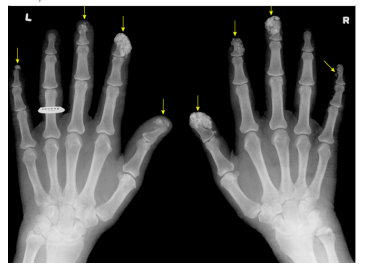

A imagem seguinte apresenta extensa calcificação

envolvendo os tecidos moles das falanges distais de ambas as

mãos, chamada de calcinose cutânea:

Fonte: UpToDate, 2023.